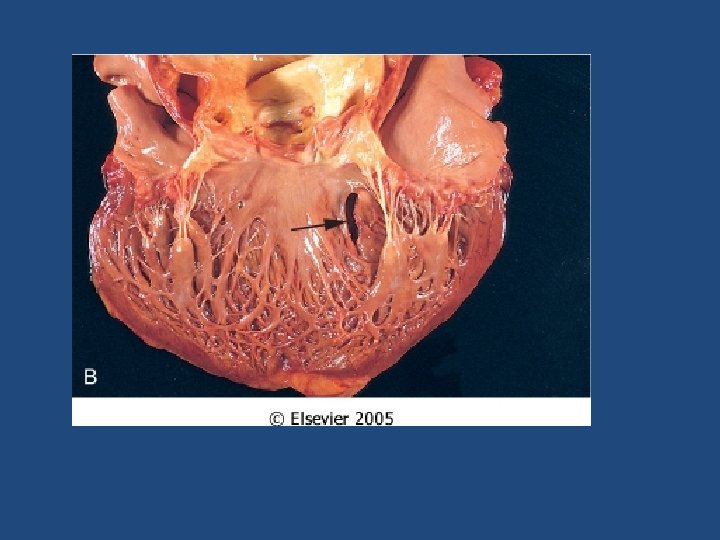

Ischemic Heart Disease Complications of MI • At least 80% will suffer: – Cardiogenic shock (>40% infarct of LV) – Congestive heart failure. CHF – Arrhythmia – Rupture of ventricle, free wall, septum, or papillary muscle – Aneurysm formation, – Mural thrombus, potentially source of emboli – Pericarditis

Chronic ischemic heart disease • Progressive heart failure due to ischemic injury, either from: – prior infarction(s) (most common) – chronic low-grade ischemia